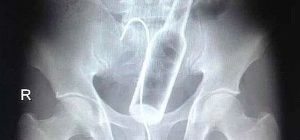

O Şişe Oraya Bakın Nasıl Girmiş…Röntgen filmlerinden çıkan akılalmaz şeyler Röntgen filmlerinden “akıl almaz şeyler Hastane koridorlarına düşenler bilir…